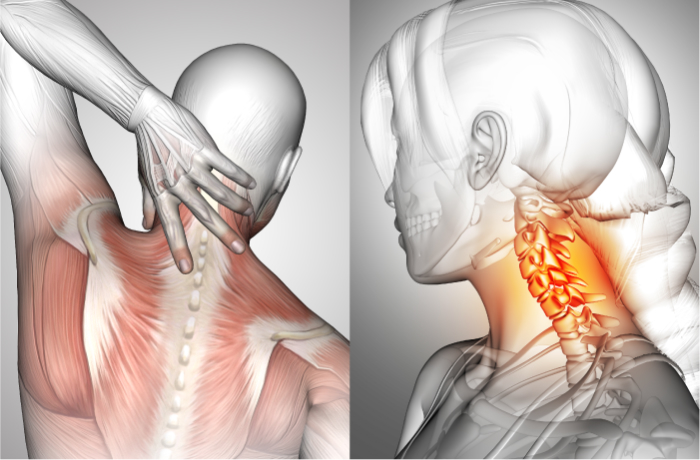

頸部の神経症状

上肢のしびれ

頸部の神経症状

上肢のしびれ

-

上肢への放散痛やしびれ、感覚障害さらには運動機能障害も引き起こされることがある

頸椎ヘルニア

-

椎骨間にある髄核が飛び出し、脊髄や神経根を圧迫して痛みなどが生じる

頸部椎間板症

-

髄核がずれ、線維輪に亀裂が入る痛みが生じ、その状態が続くことによって徐々に椎間板の水分が減少して変性を起こし、機能が低下する